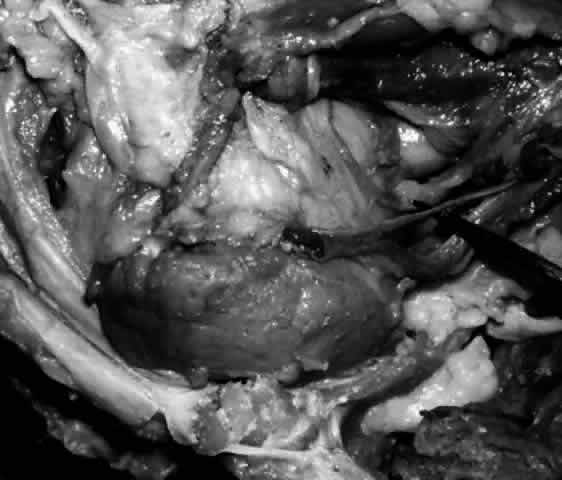

The parenchyma of the gland is made up of small lobules separated by a fine connective tissue network. The lacrimal gland has approximately 12 secretory ducts (Fig. 7), which average 0.66 mm in diameter and 2.31 mm in length.4 Two to five of them originate from the orbital lobe and six to eight from the palpebral lobe. The ductules from the orbital portion of the lacrimal gland pass through the parenchyma of the palpebral lobe before exiting into the superotemporal portion of the conjunctival fornix 4 or 5 mm above the upper border of the tarsus. One or two may open near the lateral canthus.5 Excision of the palpebral lobe may therefore interrupt drainage from the orbital lobe as well.

Fig. 7. Secretory ducts (arrow 1) of the right lacrimal gland (arrow 2) are seen passing to the palpebral conjunctiva (arrow 3). (Courtesy of James Sanderson, MD, Orkan Stasior, MD, and George Stasior, MD)